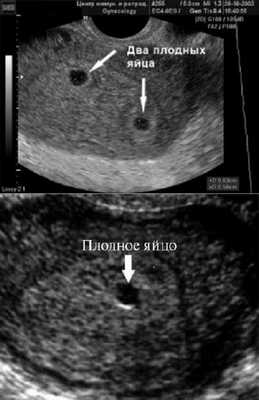

Самый ранний срок, на котором можно разглядеть с помощью трансвагинального УЗИ плодное яйцо в полости матки - это 30-й день гестации, или 4-5 акушерских недель беременности. Уровень ХГЧ крови при этом должен быть не менее 1000 мЕд/мл. В это время ещё не видно ни эмбриона, ни желточного мешка. При визуализации двух плодных яиц можно утверждать, что это дихориальная многоплодная беременность. При визуализации одного плодного яйца можно утверждать, что это монохориальная беременность. Но на этом сроке мы ещё не можем сказать сколько эмбрионов находится в каждом плодном яйце. Кроме того, во время однократного УЗИ мы ещё не можем сказать, прогрессирует ли данная беременность, так как у эмбриона ещё нет сердцебиения. Средний внутренний диаметр (СВД) плодного яйца на этом сроке 2-10 мм.

Нормальные размеры желточного мешка 2-6 мм. Если в плодном яйце визуализируются два желточных мешка, значит это монохориальная многоплодная беременность. Но если внутри плодного яйца виден один желточный мешок, а эмбрион ещё отчётливо не визуализируется, то это всё ещё может оказаться монохориальная моноамниотическая двойня.